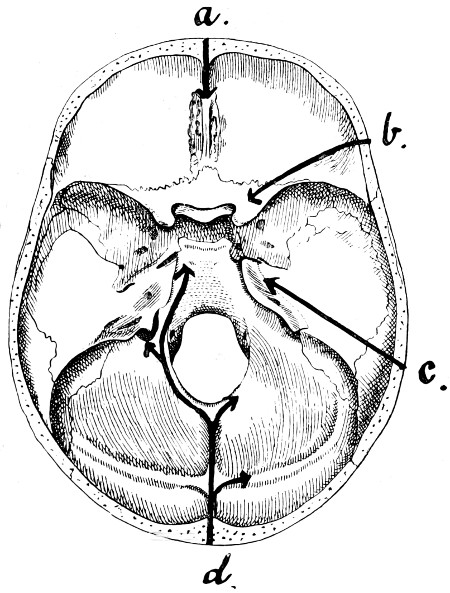

28. Illustrating the lines along which forces received on the vault are transmitted to the base 69

29 A and B. The base of the skull and the base as seen on transillumination 70, 71

30. Plan of the base of the skull 77